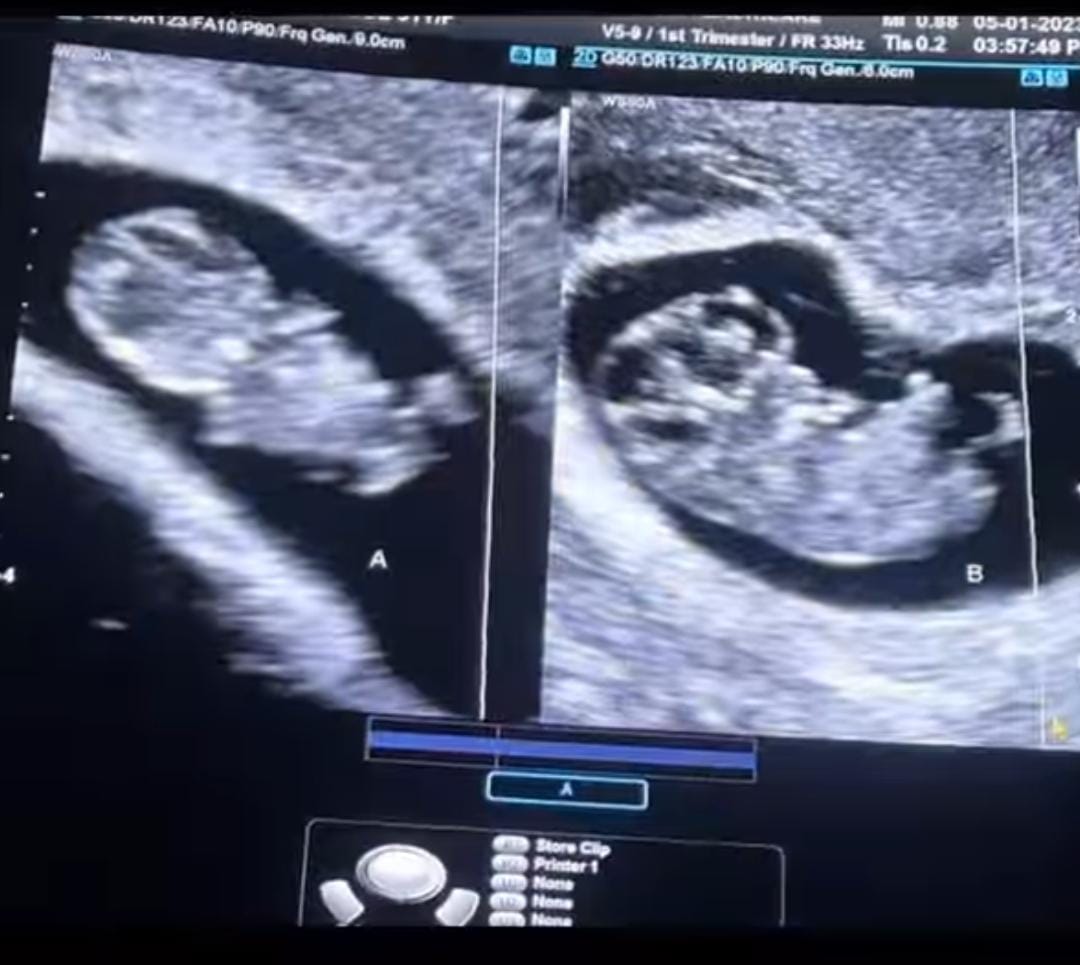

Taking to his IG handle, Gautam Rode shared a collaborative video with his wife, Pankhuri Awasthy. The video featured beautiful glimpses from Pankhuri's pregnancy journey. For instance, the video began with Pankhuri's ultrasound scans of her baby bump, wherein we could spot their twins making some movements. Afterwards, the video featured Gautam and Pankhuri, along with their doctors, making regular visits to the clinic and ultrasound checkups and many more.